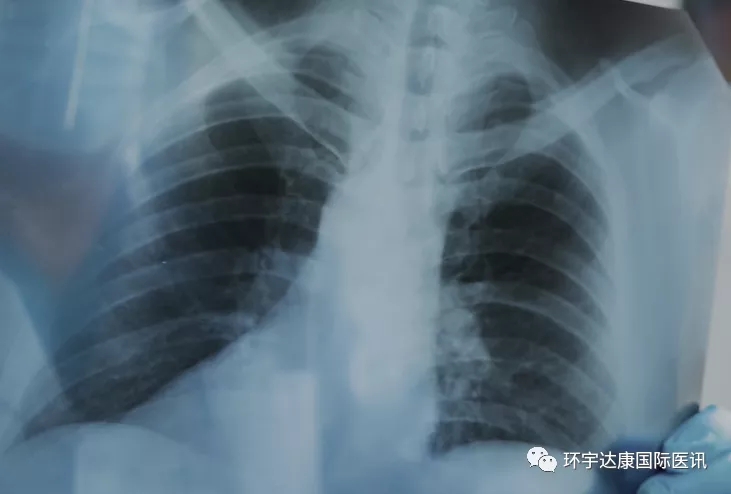

大约三年半前,72岁的Steve在头的一侧发现了一个肿块,随后的检查让他震惊,他被确诊为IV 期肺癌。肿瘤已经从左肺转移到右骨盆,以及脊柱和头骨,向全身侵袭。他不知道这一切究竟是如何发生的,因为在过去40年,他每年都会定期体检,从未发现任何问题。

6年前,David 68岁,他与妻子正在计划退休。一次打高尔夫的时候,他的球杆被夹住了,导致他出现了左胸的疼痛,像是断了一根肋骨。几天后,疼痛并没有好转,于是他去医院拍了胸片。David自己看了片子后被惊住了,除了三处肋骨骨折,当他最后看一眼时,他注意到骨架上有多个小洞,他立刻知道那是什么。作为放射科医生,虽然不经常看到它,但这是多发性骨髓瘤的典型特征,而且看起来病情已经相当晚期了。David不知道自己愣愣的坐在那里多久才恢复平静。